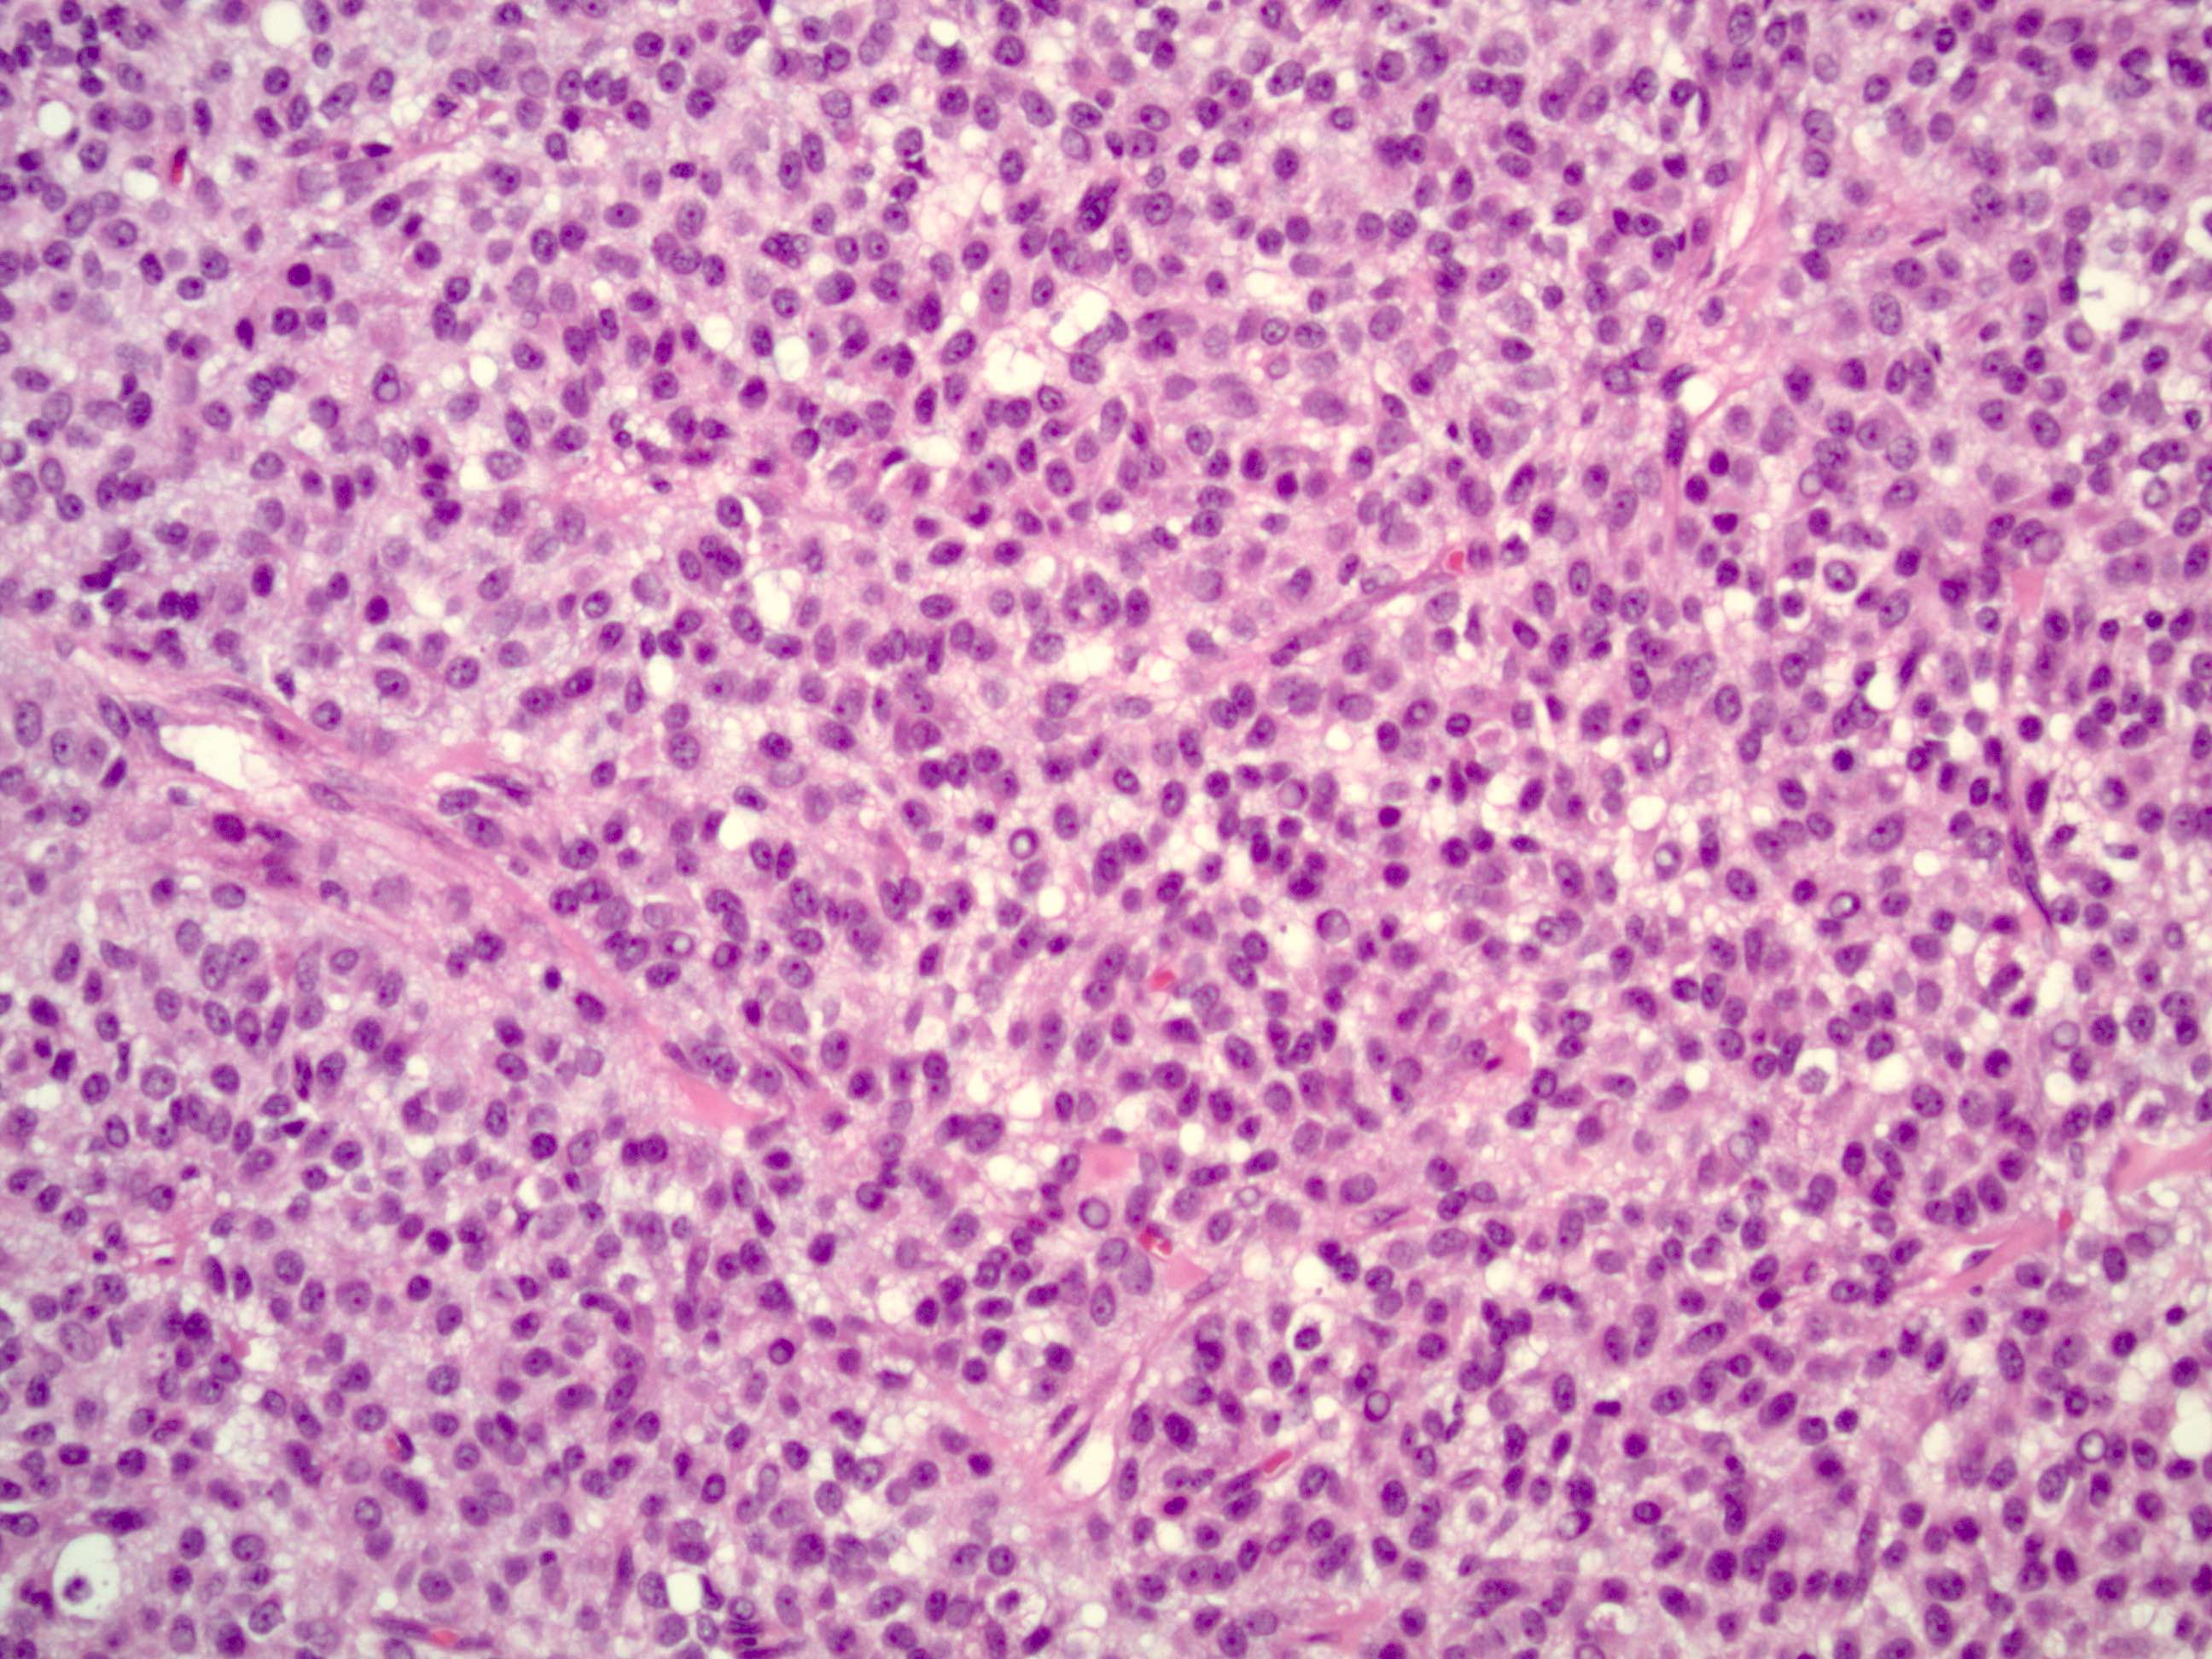

- Small, bland, cuboidal to polygonal cells with scant cytoplasm and pale, uniform angulated and usually grooved nuclei (coffee bean)

- Luteinized adult type (such as during pregnancy): rare (1%) if extensive (> 50%), plump cells with moderate to abundant eosinophilic cytoplasm, conspicuous nucleoli, no nuclear grooves, myxoid or edematous stroma; may resemble steroid cell tumor

- Mitotic activity is usually not brisk (< 3/10 high power fields)

Microscopic (histologic) images

Contributed by Shabnam Zarei, M.D. and Sharon Bihlmeyer, M.D.

AFIP images